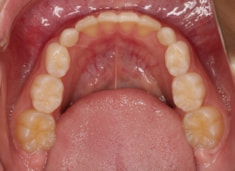

治療開始時

上下顎のギャップはありますが、顔面自体の幅径は良好な値を示していますので、スペース不足は拡大することによって解決できポテンシャルはあると考えられます。

左右の非対称もさほど強くありません。